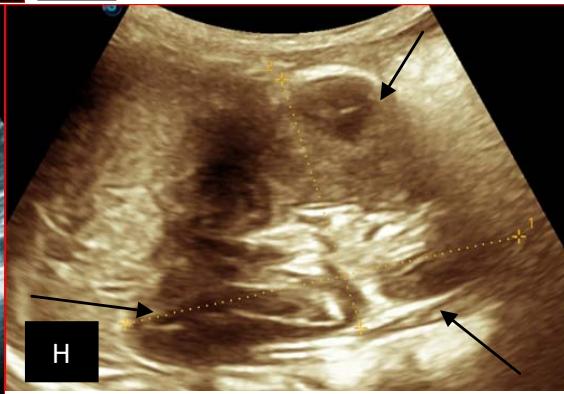

Figure 5: Abdominopelvic ultrasound control after 6 courses of chemotherapy in the same 3 year old patient with a ruptured left renal nephroblastoma; Images A, F, G, and H: show regression of the solid, endo and exo renal, left nephroblastoma mass treated with 6 courses of chemotherapy (current volume 430 ml vs) Images: B, C, and: show persistence of thrombotic permeation pan vena cava and ipsilateral renal. Image E: shows a volumetric regression of the intra-lesional hematic collection, at the tumor rupture estimated at 34.49 ml VS, Image I: represents the right kidney in B mode which is of normal echoculture. Source: Dr. Frederick Tshibasu Tshienda database.